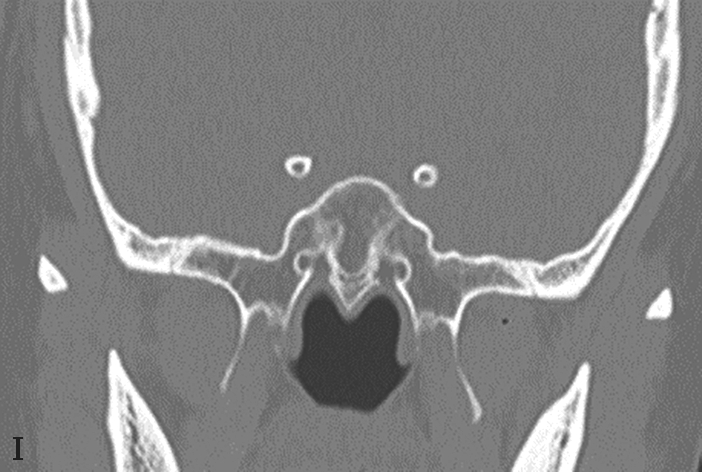

蝶窦常见解剖变异包括:①有分隔的蝶窦,可为纤维或骨性分隔分成几个不对称的部分,此变异容易导致蝶窦手术引流不完全而残留病变;②介甲型蝶窦,窦腔略有气化,发育很小,窦腔后缘与鞍结节垂直线之间尚有10mm厚骨质;③鞍前型蝶窦,蝶窦发育较小,窦腔后缘与鞍结节垂直线相齐,恰好位于蝶鞍之前,蝶鞍底大部分为松质骨;④半鞍型蝶窦,发育尚好,后上缘占鞍底前半部;⑤全鞍型蝶窦,发育良好,自鞍结节至鞍背连线的全鞍底与蝶窦只一层薄骨板;⑥枕鞍型蝶窦,与全鞍型相似,但发育更大,后缘超过鞍背垂线,蝶窦侵入枕骨使斜坡骨板更薄(图1-3-7)。

图1-3-7 蝶窦及蝶窦区解剖变异

A.颈内动脉管突入蝶窦;B.蝶窦间隔(白箭);C.左侧翼突气化;D.蝶嵴(星)、蝶骨大翼(白箭)、鞍背气化(虚箭);E.蝶骨小翼气化(白箭);F、G.鞍前型蝶窦(三角);H、I.甲介型蝶窦;J、K.鞍型蝶窦;L.Odoni气房(白箭)